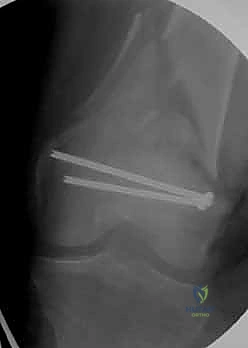

المرحلة الثالثة: إرجاع العظم (Reduction)

هذه هي الخطوة الأكثر أهمية. يقوم الدكتور هطيف بإعادة القطع العظمية المكسورة إلى مكانها التشريحي الأصلي. إذا كان الكسر ممتداً داخل المفصل، يتم تثبيت السطح المفصلي أولاً باستخدام مسامير دقيقة لضمان سطح أملس يمنع الاحتكاك والخشونة مستقبلاً.

المرحلة الرابعة: التثبيت النهائي بالشرائح والمسامير (Fixation)

يتم استخدام "شرائح الإغلاق التشريحية" (Anatomical Locking Plates) المصنوعة من التيتانيوم عالي الجودة. هذه الشرائح مصممة خصيصاً لتأخذ شكل الجزء السفلي من عظم الفخذ. يتم تمرير الشريحة أسفل العضلات وتثبيتها بمسامير تغلق داخل الشريحة نفسها (Locking Screws)، مما يوفر ثباتاً ميكانيكياً هائلاً، حتى في حالات العظام الهشة.